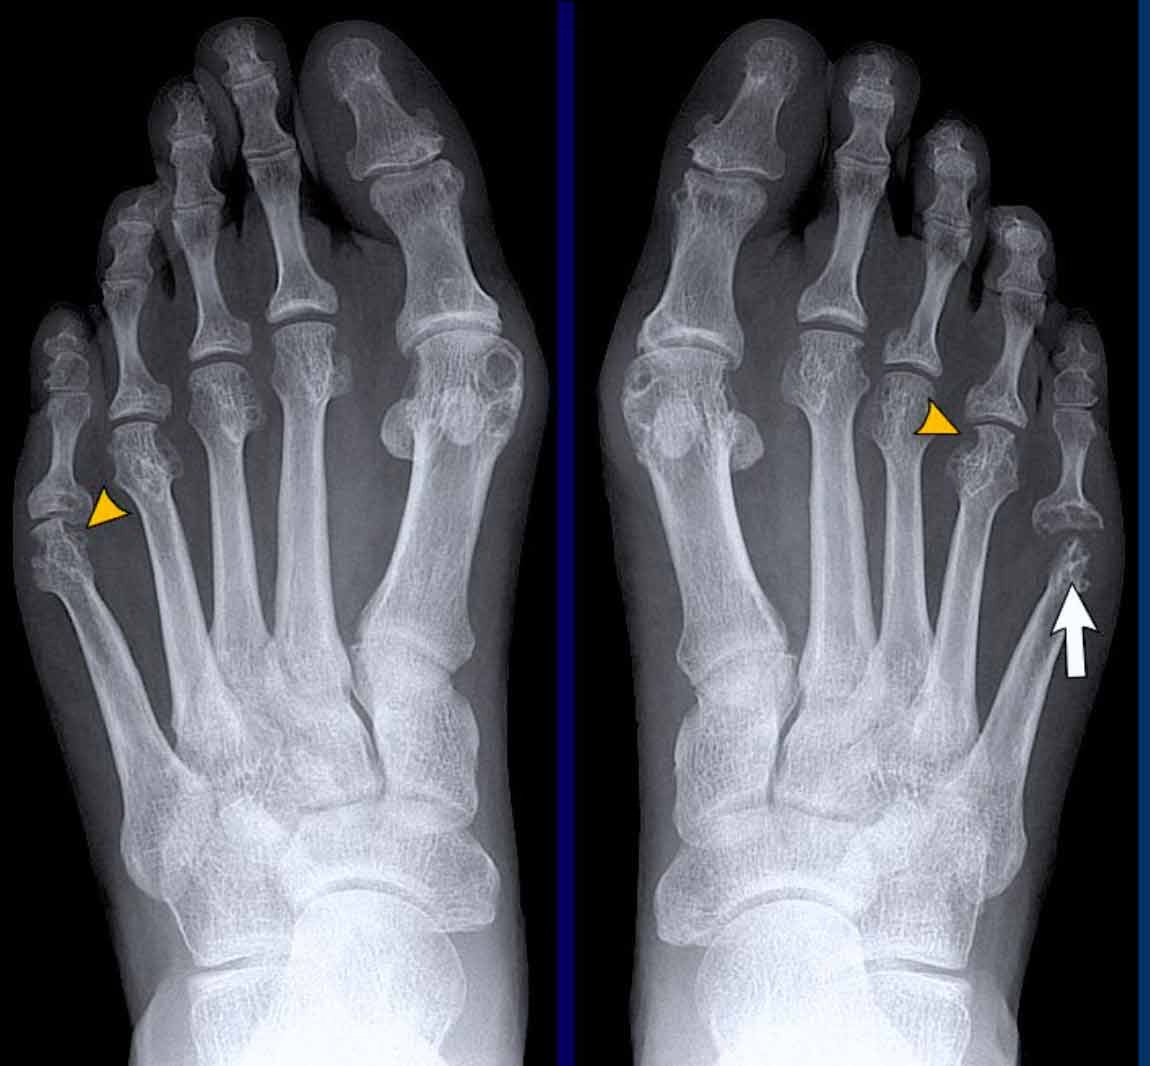

Udtrykket 'primær generaliseret slidgigt' bruges til at beskrive tilfælde af slidgigt, der opstår uden en åbenlys eller identificerbar underliggende årsag. Denne form er mere almindelig hos kvinder end mænd og har en markant stærk genetisk disposition. Det betyder, at hvis dine forældre eller søskende har det, er din risiko for også at udvikle det forhøjet. Primær slidgigt optræder i et typisk mønster og påvirker karakteristisk bestemte led i kroppen. Disse omfatter:

- Hænderne, især de yderste fingerled og tommelfingerens rodled.

- Storetåens grundled.